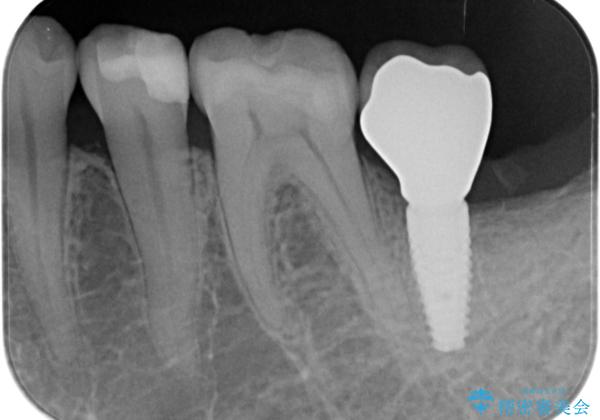

X線検査を行ったところ、セラミッククラウン下に虫歯が再発し、歯の破折も認めました。

歯の抜去を行い、骨の造成を含めたインプラントによる咬合機能の回復を図ります。

X線を撮ることで、外から見てもわからない、歯の問題点をより正確に把握することができます。